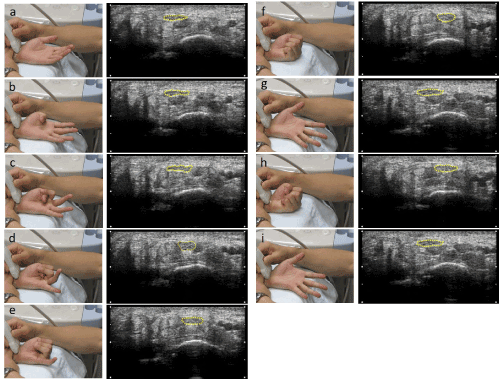

Figure 2. Finger movements and their US images

a: Hand resting on the table in the supine position (resting position)

b: Thumb flexion (finger count 1)

c: Thumb and index finger flexion (finger count 2)

d: Thumb, index finger, and middle finger flexion (finger count 3)

e: Thumb, index finger, middle finger, and ring finger flexion (finger count 4)

f: Thumb and four fingers flexion (finger count 5)

g: Extension of thumb and 4 fingers

h: Gripping movement

h: Extension of thumb and 4 fingers